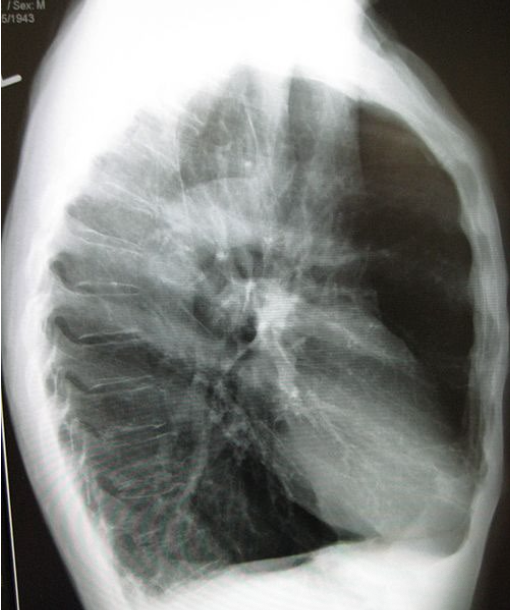

Where should the hilum be located in a lateral CXR

In the approximate centre of the radiograph

How to ensure correct position and no rotation in lateral CXR (3 points)?

Superimposition of the ribs posterior to the vertebral column

Lateral sternum with no rotation

Open thoracic intervertebral spaces